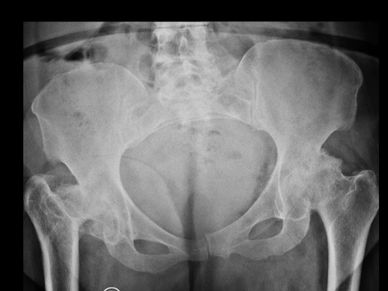

Mirá cómo recuperamos la movilidad en un caso de artrosis severa y deformidad acetabular mediante tecnología 3D de alta precisión. Planificación preoperatoria en 3D para cirugía de cadera con artrosis severa e importante deformidad acetabular. Se imprimieron biomodelos en 3D y guías para la correcta colocación de los componentes protésicos. De esta manera, se logró restaurar la longitud de las piernas y se eliminó el dolor invalidante que presentaba el paciente.

Cirugía compleja de reemplazo total de cadera.

Paciente con artrosis severa y deformidad ósea que dificultaba la colocación acetabular. Con tomografía realizamos planificación 3D y diseñamos una guía quirúrgica personalizada impresa en 3D. En quirófano replicamos el plan: posicionamiento preciso del componente y restauración del centro de rotación. La tecnología 3D aporta más precisión, seguridad y predictibilidad en casos complejos.